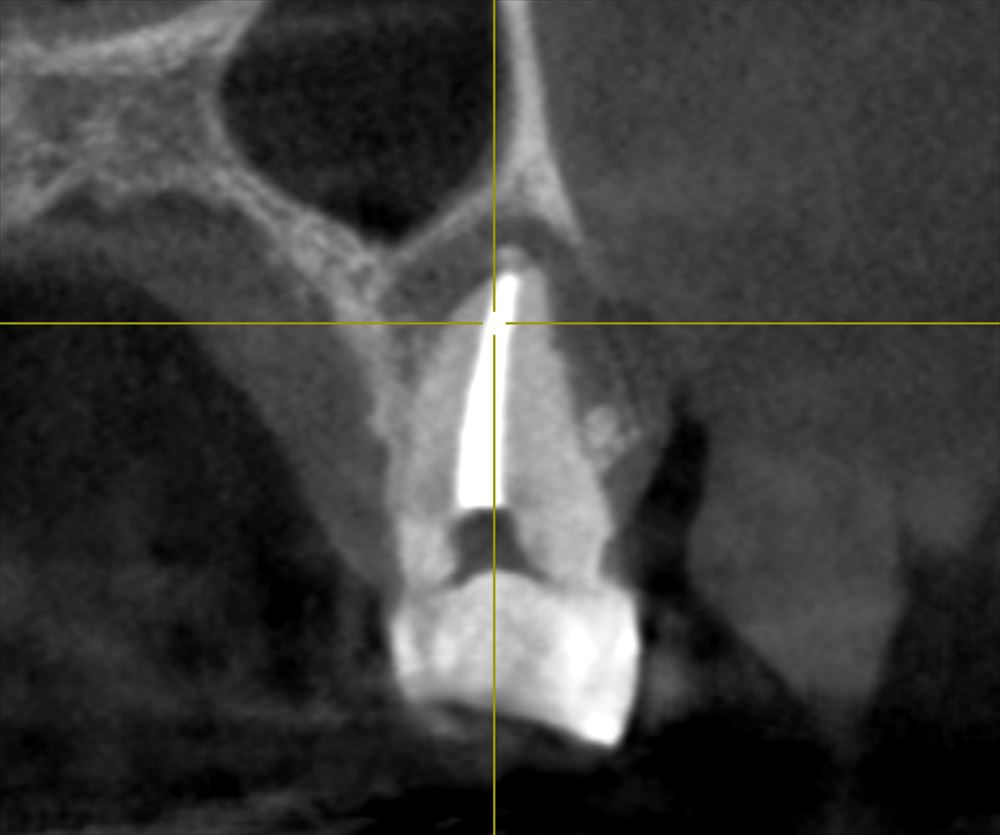

CTでも近遠心で確認

頬側の骨がないですね。この治療で再生してくるはずです。